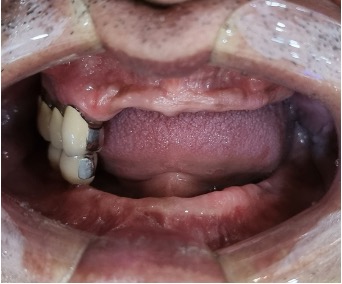

디지털 풀아치 임플란트(상악) (73세 남성)

2023. 10. 23 수술전 인터뷰 "틀니 사용으로 어떤 어려움을 겪고 계셨나요?"